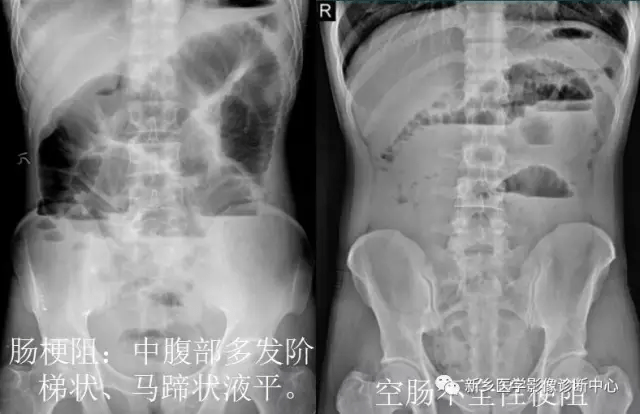

13 肠梗阻

1.肠梗阻:中腹部多发阶梯状 , 马蹄状液平 。 2.空肠不全性梗阻 。

1.空肠不全性梗阻:空肠扩展呈弹簧状 。 2.空肠机械性梗阻:弹簧征